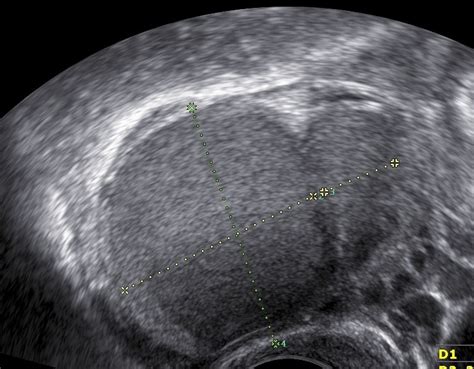

- Proliferačná fáza (5. - 15. deň cyklu): Súvisí s postupným dozrievaním vajíčka v jednom z vaječníkov a produkciou estrogénov, ktorý vytvárajú vaječníky, aby sa v maternici začala tvoriť nová mäkká sliznica. Krčok maternice produkuje viac hlienu. Sliznica maternice má na konci proliferačnej fázy hrúbku asi 3 - 4 mm. V celom rozsahu ju prestupujú žliazky, ktoré v reze vyzerajú ako úzke a priame trubičky.

- Sekrečná fáza (16. - 27. deň cyklu): Sliznica ďalej mohutnie a pri svojom vrchole dosahuje 5 - 7 mm. V tomto období sa prázdny folikul uzatvára a premieňa na žlté teliesko, ktoré vytvára estrogény a hlavne progesterón ovplyvňujúci rast maternicovej sliznice. Na konci sekrečnú fázy sú v tele vytvorené ideálne podmienky pre zahniezdenie oplodneného vajíčka.

Endometrium je vnútorná výstelka maternice, zatiaľ čo myometrium je svalová vrstva maternice. V prípade adenomyózy však dochádza k prerastaniu endometriálneho tkaniva do myometria.

Adenomyóza je ochorenie, pri ktorom tkanivo vystielajúce dutinu maternice (endometrium) začne prerastať do hrúbky jej svalovej vrstvy (myometrium). V dôsledku toho sa bunkové štruktúry endometria ocitnú vnútri svalu, kde naďalej reagujú na hormonálne zmeny počas menštruačného cyklu. Rast tkaniva vedie k zahusteniu stien maternice, zápalovej reakcii, opuchu a časom k vzniku uzlín, fibrózy a zvýšenej citlivosti.

- Endometrium: Vnútorná sliznica maternice.

- Myometrium: Hrúbka svalovej vrstvy maternice.